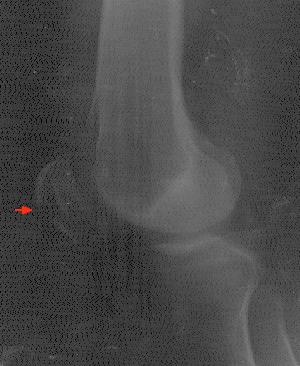

Eine kleine Unachtsamkeit - wohl begünstigt davon, daß gerade ein Hagelschauer niederging - führte dazu, daß ich gestolpert bin, und dummerweise stürzte ich exakt mit dem Knie auf eine Bordsteinkante. Zunächst konnte ich mit gestrecktem Knie noch laufen und auch Ein- und Auskuppeln beim Autofahren funktionierte bei vorsichtigen Bewegungen schmerzfrei. Doch am Hotel in Falkirk wurden die Schmerzen schlimmer und es wurde klar, daß wohl doch ein größerer Schaden vorliegen müsse. Daraufhin erfolgte ein Der Pfeil markiert die Kniescheibe Besuch in der Notfallstation Falkirk, wo sich im Röntgenbild herausstellte, daß die Kniescheibe gebrochen war.

Auf Details der Heimreise soll hier nicht weiter eingegangen werden, seit dem 6.1. werde ich jedenfalls in der orthopädischen Fachklinik in Wetter behandelt, wo am 7. im Rahmen einer Operation eine Fixierung der Kniescheibe mit einer Art Drahtkäfig erfolgte. Insgesamt wird der Klinikaufenthalt wohl etwa zwei Wochen dauern, die vollständige Rehabilitierung ungefähr zwei bis drei Monate. Spätestens dann - hoffentlich schon eher, was sich noch zeigen wird - sollten wieder Spielbesuche drin sein.